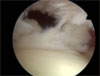

Zerwanie widziane podczas artroskopii ( małe i duże).

Rekonstrukcja przyczepu mięśnia nadgrzebieniowego i innych z obręczy kości ramiennej może być wykonana artroskopowo lub otwarcie. Mogą być używane kotwice lub przy otwartej rekonstrukcji nici wchłanialne.